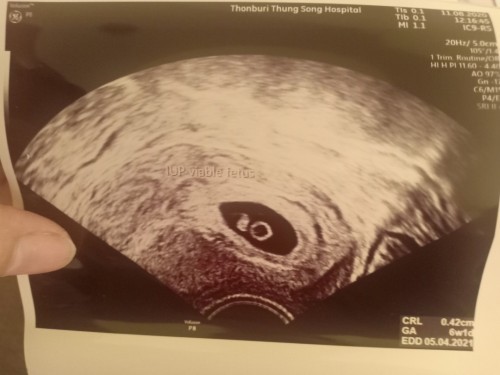

เหมือนกันค่ะ แต่ พอเข้า 9 week เจอตัวอ่อนค่ะ สู้ๆนะคะ น้องน่าจะตัวเล็กอยู่เลยยังมองไม่เห็น

ตอนนั้นเจอเเค่ถุงอาหารเหมือนกันค่ะ ไม่ต้องกังวลนะคะ เดี๋ยวสักพักใหญ่ๆ ก็ตะเจอน้องค่ะ

ตอน6wเราก็ไม่เจอค่ะหมอเลยนัดอีก3สัปดาห์ค่ะ ถึงจะเห็นตอนนี้ก็12w+6d

ของเราซาวด์เห็นตอน6วีค 1วันค่ะ เห็นน้องตัวเล็กมากค่ะ แม่ใจเย็นๆนะคะ รอบหน้าก็เห็นค่ะ

เราซาวตอน5+6ก็ไม่เจอเหมือนกันคะหมอให่รออีก2สัปดาห์ซาวใหม่หมอบอกครรภ์ยังอ่อน

4วีคเจอแต่ถุง เจอน้องพร้อมเสียงหัวใจตอน8สีคพอดีค่ะเเม่อย่าพึ่งกังวลไปนะคะ